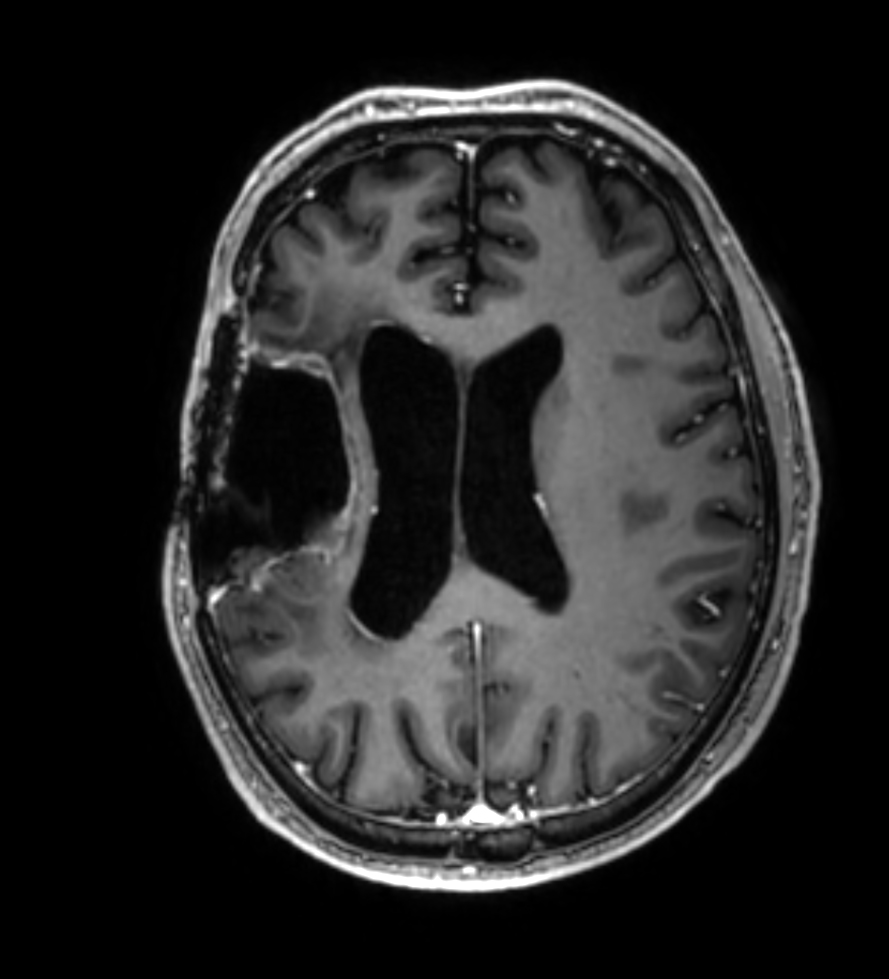

3D T1w TFE - Axial reformat